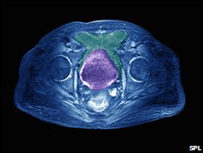

Homens negros que vivem na Inglaterra correm risco três vezes maior de sofrer de câncer da próstata do que brancos, segundo estudo realizado por pesquisadores da Universidade de Bristol. Os negros também tendem a ser diagnosticados cinco anos mais cedo, de acordo com a análise de todos os casos registrados nas cidades inglesas de Londres e Bristol. O responsável pelo estudo da Universidade de Bristol, Chris Metcalfe, diz que estas são as primeiras evidências produzidas na Grã-Bretanha sobre diferenças entre índices de câncer da próstata em negros e brancos. Segundo o especialista, suspeitava-se anteriormente que homens negros demoravam mais para procurar o médico - por isso, o estágio mais avançado da doença quando finalmente diagnosticada. "A evidência indica que os negros estavam, na verdade, se apresentando antes", afirma Metcalfe. "Há muito poucos fatores de risco conhecidos para o câncer da próstata, mas está começando a parecer que ser negro é um fator de risco." ONGs ligadas ao câncer afirmam que a descoberta pode resultar em uma melhor assistência para grupos sob maior risco. Análise Os pesquisadores dizem que especialistas americanos já haviam relatado um maior índice de câncer de próstata entre negros. De acordo com artigo publicado pelos pesquisadores na revista científica British Journal of Cancer, os resultados não podem ser explicados por questões como o acesso a exames diagnósticos, conhecimento sobre a condição ou programas de testes preventivos. Durante o estudo, não ficou claro inicialmente se havia uma incidência "genuinamente" maior de câncer de próstata em negros ou se eles simplesmente tinham mais chance de ser diagnosticados. Mas quando os registros médicos foram analisados detalhadamente, os pesquisadores verificaram que negros e brancos tinham níveis parecidos de conhecimento sobre o câncer da próstata e sintomas semelhantes. Eles também demoraram mais ou menos o mesmo tempo para consultar um clínico geral. No entanto, foram encontradas evidências de que negros tinham maior probabilidade de fazer o teste PSA (sigla em inglês para antígeno prostático específico) antes de apresentar qualquer sintoma. O PSA não é um teste para diagnosticar o câncer, mas pode indicar anormalidades. Suscetibilidade Ao comentar as razões pelas quais homens negros estariam sendo diagnosticados mais cedo, os pesquisadores dizem que há uma maior probabilidade de que o câncer da próstata em pessoas mais jovens seja resultado de uma maior suscetibilidade biológica à doença. Os especialistas estão agora realizando mais pesquisas para ver se há diferenças nos índices de sobrevivência apresentados pelos dois grupos. Estudos para verificar se os exames de PSA deveriam ser usados de forma rotineira para a identificação de novos casos também estão sendo realizados e há a possibilidade de que os testes sejam recomendados para grupos de alto risco. Joanna Peak, representante da entidade beneficente britânica Cancer Research UK, que incentiva pesquisas na área, afirma que o câncer de próstata é o mais comum entre homens britânicos. "O estudo indica que há uma diferença biológica real entre grupos étnicos, e esse conhecimento pode potencialmente levar a tratamentos melhores para homens sob maior risco", diz Peak. "Recomendamos a todos os homens que visitem seus clínicos gerais se estiverem apresentando qualquer sintoma possível de câncer da próstata, por exemplo, problemas ao urinar", acrescentou Anna Jewell, da entidade beneficente The Prostate Cancer Charity. "Isso demonstra a necessidade de continuarmos a trabalhar para elevar a consciência sobre os maiores riscos de câncer da próstata entre os homens negros", completou Jewell. | NOTÍCIAS RELACIONADAS Exercício pode piorar câncer de próstata, diz estudo14 abril, 2008 | BBC Report 'Altas doses de vitamina C podem conter câncer'05 agosto, 2008 | BBC Report Celebridades fazem evento histórico contra câncer06 setembro, 2008 | BBC Report Britânicos desenvolvem teste barato para câncer de mama17 setembro, 2008 | BBC Report Amamentar reduz risco de câncer de mama, diz estudo29 setembro, 2008 | BBC Report Bebês grandes 'correm mais risco de desenvolver câncer de mama'30 setembro, 2008 | BBC Report LINKS EXTERNOS A BBC não se responsabiliza pelo conteúdo dos links externos indicados. | |||||||||||||||||||||||||||||||||||||||||||||||||||||||||||||||||||||||||||||||||||||||||||||||||||||||||||||